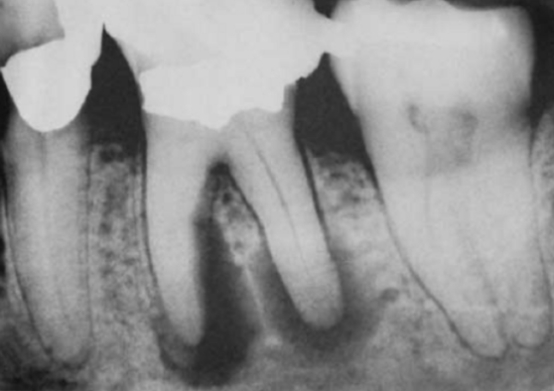

根尖周病

根尖周病是牙齿根尖周围组织的一种炎症性疾病,可以是细菌感染,也可以是创伤、牙隐裂等问题导致,严重的根尖周病可大量吸收破坏牙齿根尖周围的骨组织,导致患牙无法固定在牙槽骨里而松动。

未及时治疗的龋病、牙髓病,细菌可沿根管内感染到根尖,因此为了有效防止根尖周病,对于龋齿、牙髓炎等疾病需要尽早治疗,避免炎症发展至根尖。

根尖片上显示严重的根尖周炎,可能导致牙齿无法保留